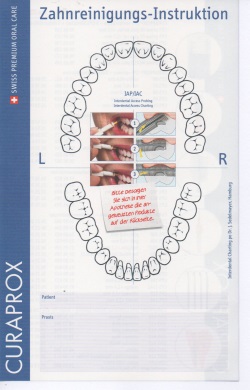

Der besonders intensive Behandlungsabschnitt "Motivation und Instruktion" beinhaltet eine auf den einzelnen Patienten abgestimmte Beratung und Demonstration verschiedener zur Zahnpflege dienender Hilfsmittel: es werden verschieden Zahnbürstenarten erklärt, der Gebrauch verschiedener Hilfsmittel zur Pflege der Zahnzwischenräume wird an den eigenen Zähnen gezeigt. Hierbei kommen z.B. verschiedene Zahnseidearten zur Anwendung, aber auch besondere Bürsten zur Reinigung dieser den normalen Zahnbürsten unzugänglichen Bereiche sind seit vielen Jahren erprobt und im Einsatz. Für uns hat sich der Gebrauch eines Systems zur Messung der Größe der Zwischenräume und der darauf abgestimmte Einsatz verschieden großen Bürstchen bewährt:

Beim Patienten werden alle Zahnzwischenräume mit einer Messsonde ausgemessen. Je nach Größe des Raumes zeigt die Messsonde eine zugeordnete farbliche Markierung (hier: z.B. "gelb")

Beim Patienten werden alle Zahnzwischenräume mit einer Messsonde ausgemessen. Je nach Größe des Raumes zeigt die Messsonde eine zugeordnete farbliche Markierung (hier: z.B. "gelb")

Die gemessenen Farben werden in einem Patientenbefundbogen aufgeschrieben

Die gemessenen Farben werden in einem Patientenbefundbogen aufgeschrieben

Der Zahnarzt bestimmt die für den erhobenen Befund passenden Bürstchengrößen. Auf der Rückseite des Befundblattes kann direkt für den Einkauf in der Apotheke das passende System angekreuzt werden.

Der Zahnarzt bestimmt die für den erhobenen Befund passenden Bürstchengrößen. Auf der Rückseite des Befundblattes kann direkt für den Einkauf in der Apotheke das passende System angekreuzt werden.